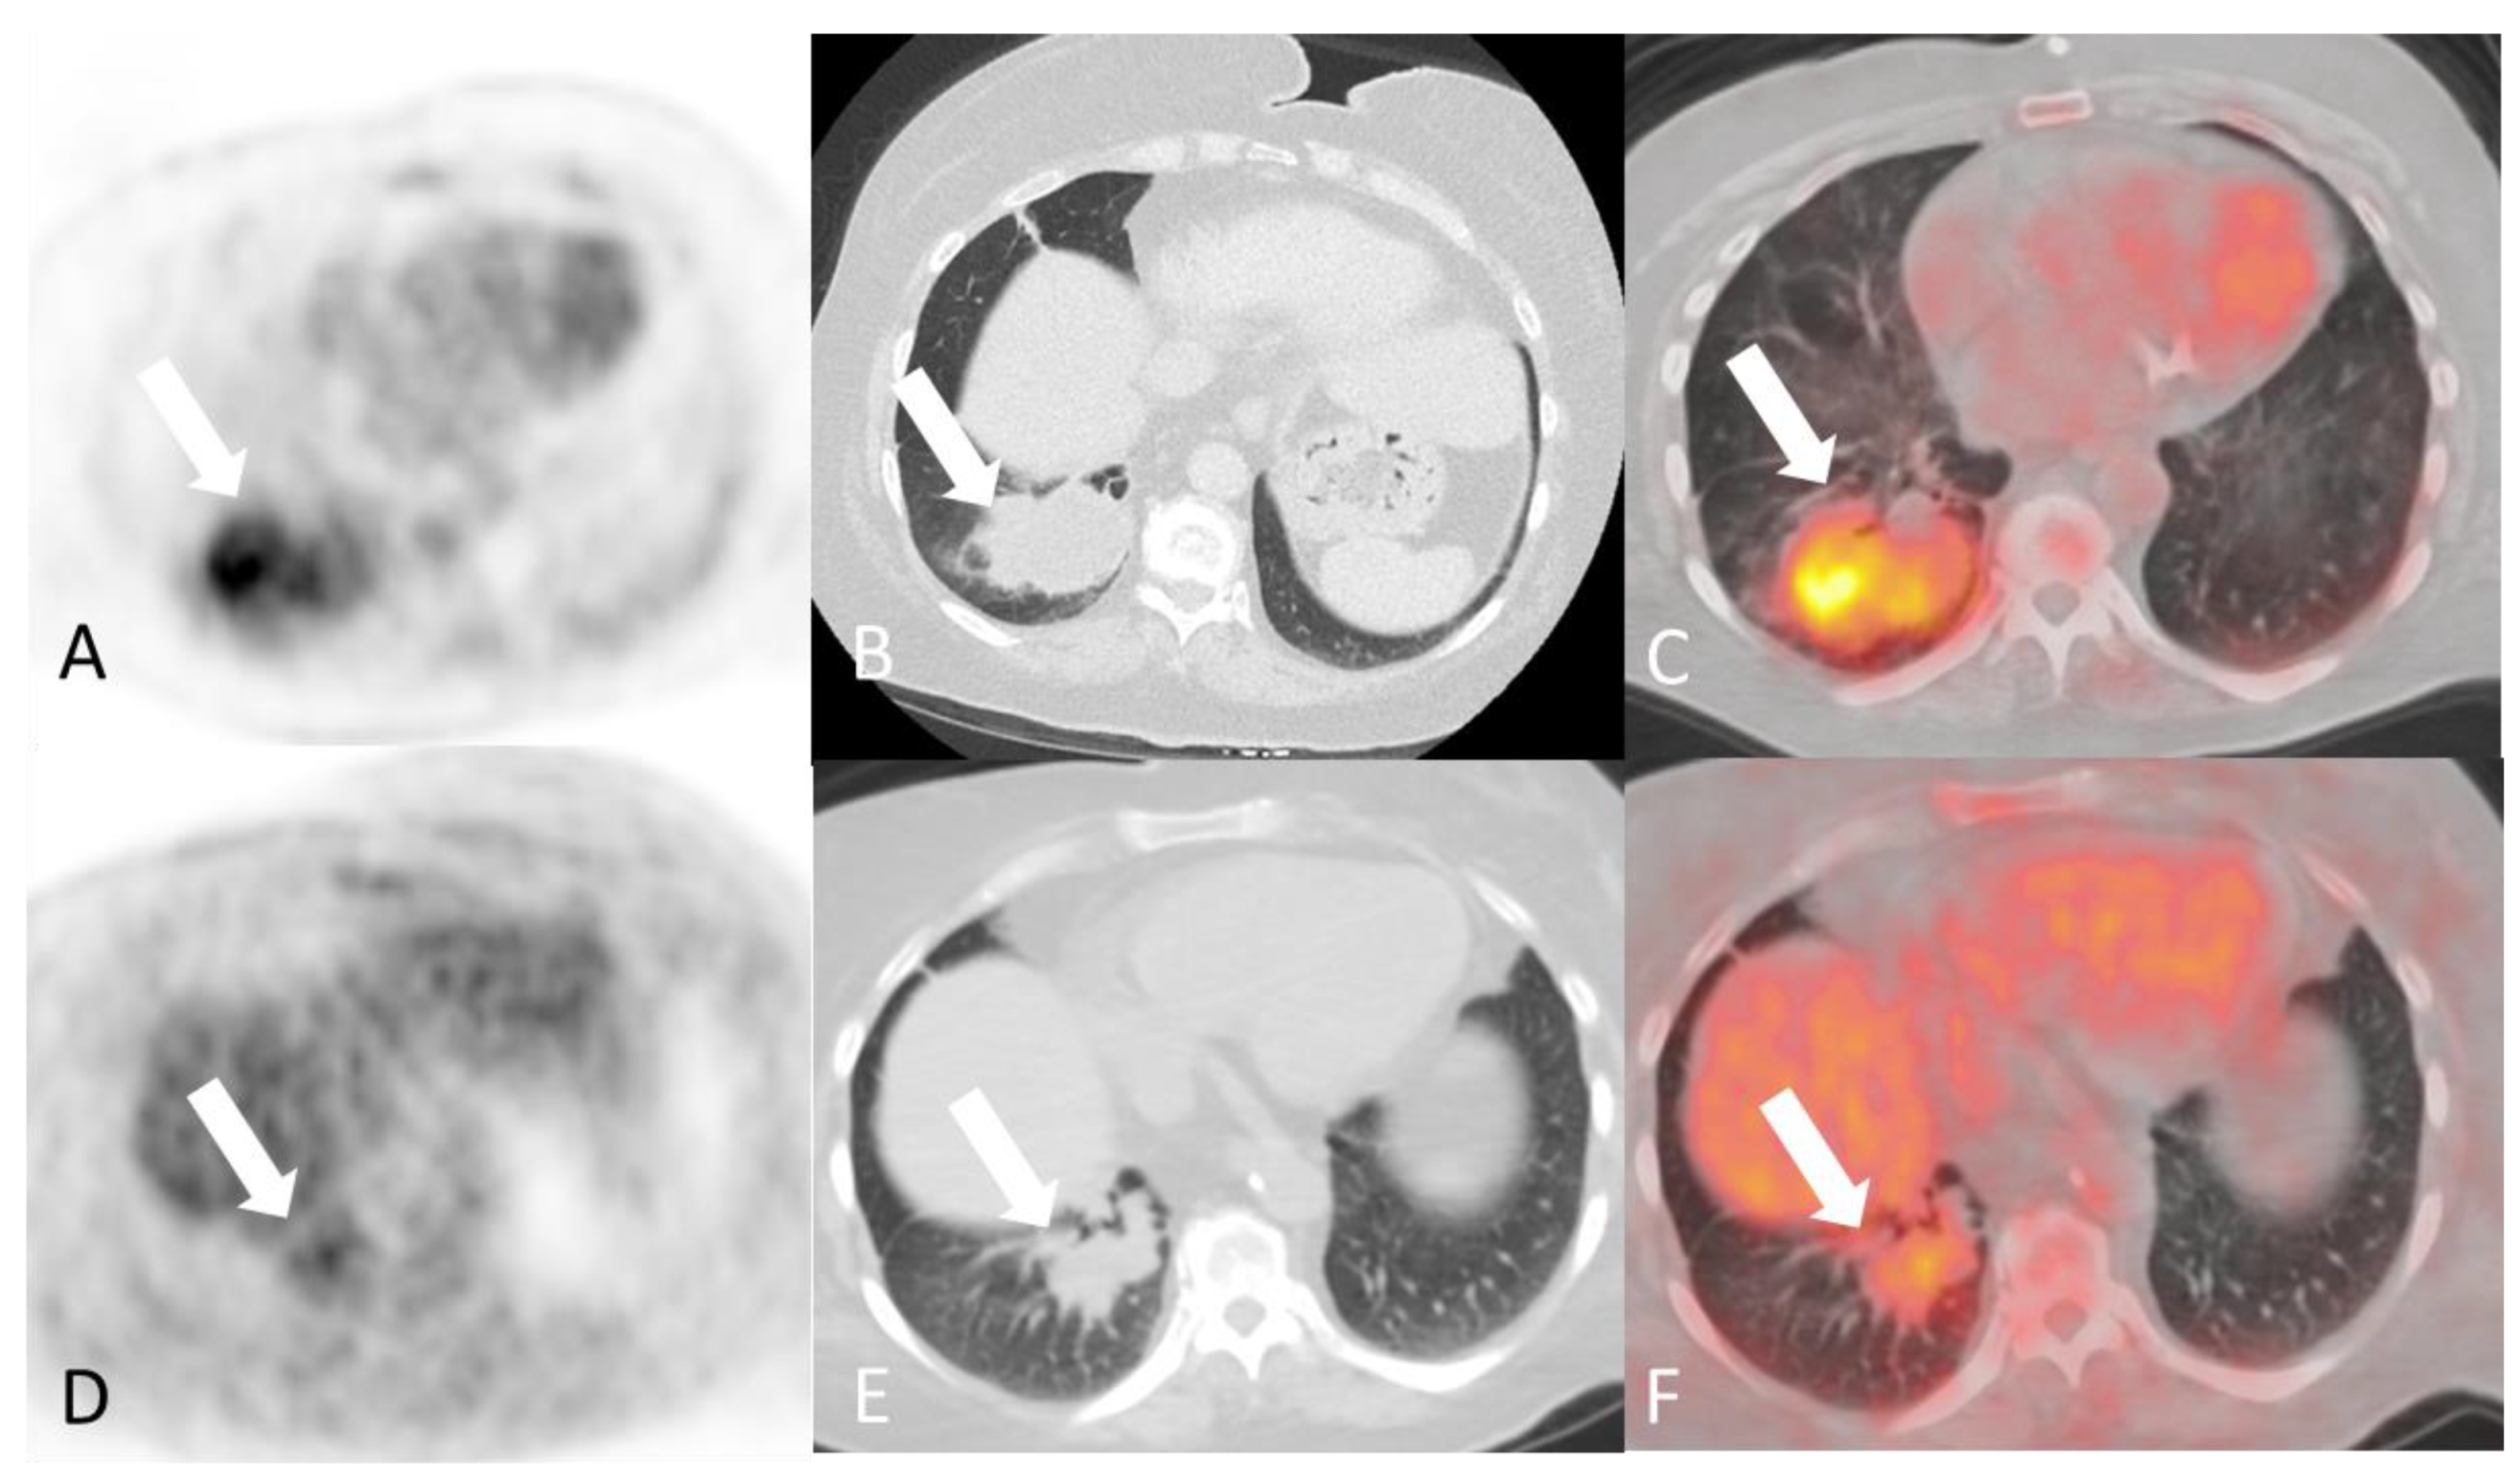

2.3.1. Granulomatosis with Polyangiitis

- Tee, Q.X.; Wong, A.; Nambiar, M.; Lau, K.K. Granulomatosis with polyangiitis: Common and uncommon presentations. J. Med. Imaging Radiat. Oncol. 2022, 66, 1089–1096. [Google Scholar] [CrossRef] [PubMed]

- Guneyli, S.; Ceylan, N.; Bayraktaroglu, S.; Gucenmez, S.; Aksu, K.; Kocacelebi, K.; Acar, T.; Savas, R.; Alper, H. Imaging findings of pulmonary granulomatosis with polyangiitis (Wegener’s granulomatosis): Lesions invading the pulmonary fissure, pleura or diaphragm mimicking malignancy. Wien. Klin. Wochenschr. 2016, 128, 809–815. [Google Scholar] [CrossRef] [PubMed]

- Castaner, E.; Alguersuari, A.; Andreu, M.; Gallardo, X.; Spinu, C.; Mata, J.M. Imaging findings in pulmonary vasculitis. In Seminars in Ultrasound, CT and MRI; WB Saunders: Philadelphia, PA, USA, 2012; Volume 33, pp. 567–579. [Google Scholar] [CrossRef]

- Mohammad, A.J.; Mortensen, K.H.; Babar, J.; Smith, R.; Jones, R.B.; Nakagomi, D.; Sivasothy, P.; Jayne, D.R.W. Pulmonary Involvement in Antineutrophil Cytoplasmic Antibodies (ANCA)-associated Vasculitis: The Influence of ANCA Subtype. J. Rheumatol. 2017, 44, 1458–1467. [Google Scholar] [CrossRef]

- Soussan, M.; Abisror, N.; Abad, S.; Nunes, H.; Terrier, B.; Pop, G.; Eder, V.; Valeyre, D.; Sberro-Soussan, R.; Guillevin, L.; et al. FDG-PET/CT in patients with ANCA-associated vasculitis: Case-series and literature review. Autoimmun. Rev. 2014, 13, 125–131. [Google Scholar] [CrossRef]